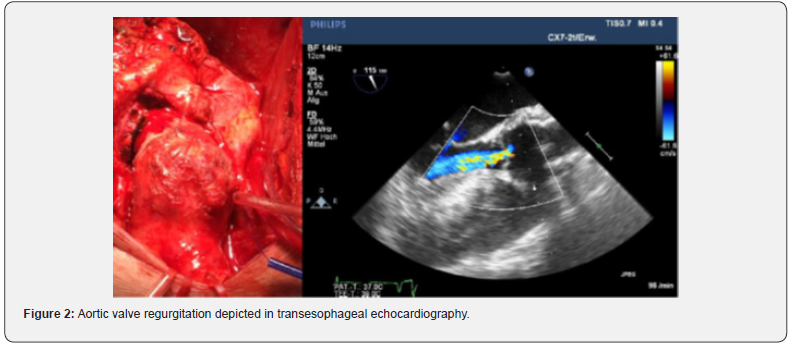

A 59-year-old female patient suffering from recurrent chest pain after acute Stanford Type A aortic dissection (TAAD) presented at our outpatient clinic. Four months prior to this consultation, the patient underwent emergency surgery with aortic root remodeling and replacement of the ascending aorta in deep-hypothermic arrest at another centre. The postoperative period was complicated by pulmonary insufficiency with prolonged ventilation. At the present visit in our department, a control contrast-enhanced computed tomography was performed showing a rest dissection starting at the distal ascending aorta was seen (Figure 1). Additionally a moderate aortic valve regurgitation was seen at transesophageal echocardiography (Figure 2). The patient was urgent taken to the operating theatre for complete open repair. Cardiopulmonary bypass was initiated by re-cannulation of the right axillary artery and the right femoral vein. Hypothermic circulatory arrest at 17.7°C was instituted for implantation of a frozen elephant trunk (E-vita OPEN PLUS Hybrid Stentgraft System 24mm with a stentgraft length of 130mm; Jotec GmbH, Hechingen, Germany), arch replacement and replacement of the aortic valve using a rapid-deployment valve system (23mm) after removing the native aortic valve leaflets. Antegrade brain perfusion was performed for 42 minutes and cross-clamp time was 93 minutes. The postoperative course was uneventful and respirator weaning was achieved within 5 hours. On postoperative day 2, the patient was transferred to the general ward. The patient was discharged home on postoperative day 14 showing excellent aortic valve function, without regurgitation and optimal aortic repair (Figure 3,4). On 6 months follow-up these data could be confirmed (Figure 5).